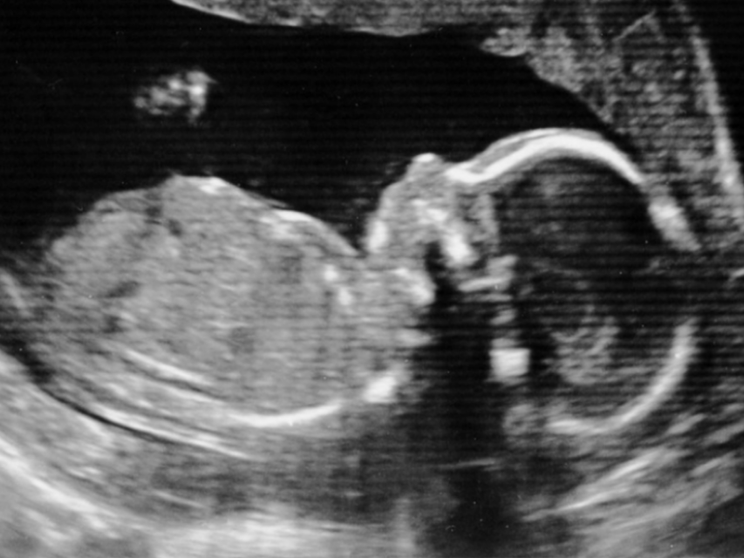

Le nuove linee guida per applicare la legge 40 sulla procreazione assistita mettono ordine nella materia dopo sentenze e provvedimenti che si sono succeduti negli anni. Con alcune sorprese